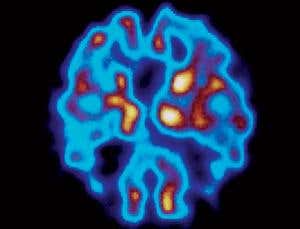

PET scans could be used to detect Alzheimer’s plaques before symptoms of dementia appear (Image: Tim Beddow/SPL)

Over a century later, research into Alzheimer’s disease still revolves around efforts to understand those mysterious plaques and tangles. Despite decades of work, no effective treatment exists, never mind a cure. The world’s population is ageing, so that search is becoming more urgent. Alzheimer’s disease is now recognised as the most common form of dementia, with over 25 million people living with the disease worldwide, and that number is expected to pass 100 million by 2050 (see diagram). Yet today, even definitively diagnosing the disease can still only be done at autopsy.

The situation is starting to change, however. Thanks to a new imaging technique, the plaques can now…